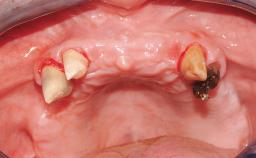

Immediate Loading of Eight Implants in the Maxilla and Six Implants in the Mandible and Final Restoration with Three-Unit and Four-Unit FDPs

Extensive scientific evidence has confirmed that immediately loaded implants with fixed full-arch provisional restorations can osseointegrate with success rates similar to conventionally or delayed loaded implants. A number of immediate-provisionalization techniques for edentulous jaws have been described. Some protocols differ when it comes to prefabricated provisional templates versus complete denture conversion; intrasurgical impressions versus direct relining; and cemented versus screw-retained provisional restorations. In this context, complete-denture conversion has been proposed for either intrasurgical impressions or direct relining. Another possibility is the utilization of a prefabricated provisional to be adapted either in the mouth (by direct relining) or in the laboratory (on a working model obtained from an intrasurgical impression).

Case Type Edentulous Maxilla

Defining Characteristics Fully edentulous upper jaw to be rehabilitated with four or more implants

Bone Volume Horizontally and vertically sufficient